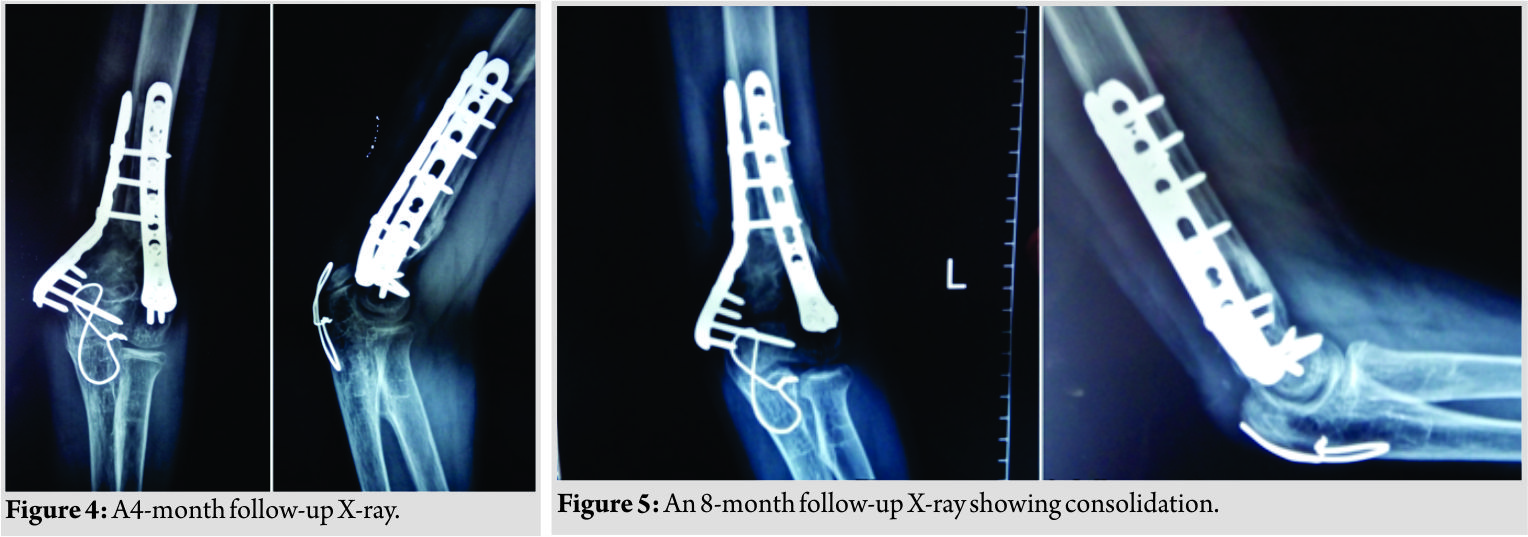

A 16-year-old student was brought to the emergency with a history of trivial fall following which he developed pain and swelling in his left distal arm. X-rays showed a fracture of distal humerus with a lytic lesion involving the distal third of the humerus (Fig.1).Hematological and biochemical investigations were normal. The arm was initially stabilized in a U slab and the patient was taken for fixation in routine OT. Under general anesthesia, the patient was placed in lateral position. Posterior midline incision was taken from distal third of humerus to proximal ulna. Ulnar nerve isolated and olecranon osteotomy was performed to expose the fracture site in distal humerus. A cavity filled with homogenous grayish-white nodular membrane was found. Entire cavity was curetted and the tissue removed was sent for histopathological examination. Fracture margins were freshened. Fibular graft was harvested from the ipsilateral lower limb. The cavity was filled with fibular strut graft. Fixation of the fracture was done with bicolumnar plating (lateral column – posterior and medial column – medial). K-wire tension band wiring was done for olecranon osteotomy (Fig. 2).

Wound closed in layers. The limb was immobilized in above elbow slab. Post-operative period was uneventful. Suture removal was done after 2 weeks. Passive-assisted elbow range of motion was started at 2 weeks as per pain tolerance. Active range of motion was started after 4 weeks. Histopathology report confirmed the diagnosis of SBC. The patient had good functional range of motion at 4 months (10–130) (Fig. 3).

There was no donor site morbidity. Follow-up radiographs after 8 months showed full integration of fibular graft (Fig. 4 and 5).